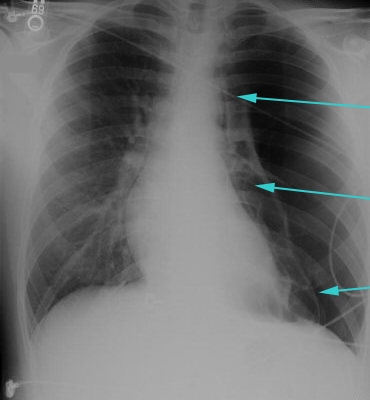

Large left pneumothorax with visible pleural line and absence of lung markings beyond the line

From the collection of Dr Ami Rubinowitz; used with permission